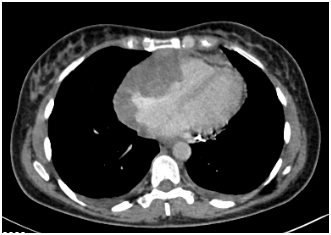

A 55-year-old African American woman presented with a one-month history of progressive exertional dyspnea and chest tightness. She had no significant past medical history. An echocardiogram revealed a large pericardial effusion and features of cardiac tamponade. A cardiac CT scan (Figure 1A) showed a mass at the pericardium extending into the right ventricular myocardium. Multiple bilateral lung nodules were noted with the largest measuring 1.6 cm in diameter.

Figure 1A CT scan shows a mass at the pericardium extending into the right ventricular myocardium.

A pericardial catheter was placed and a large bloody effusion was drained. A cardiac MRI (Figure 1B) revealed a 10 cm infiltrating soft tissue mass involving the right atrium and right ventricle. The right coronary artery was encased and attenuated. The mass extended into the atrioventricular groove and infiltrated the roof of the right ventricle. The anterior surface of the aortic root was also encased. Heterogeneous enhancement of the mass suggested a vascular lesion suggestive of angiosarcoma.